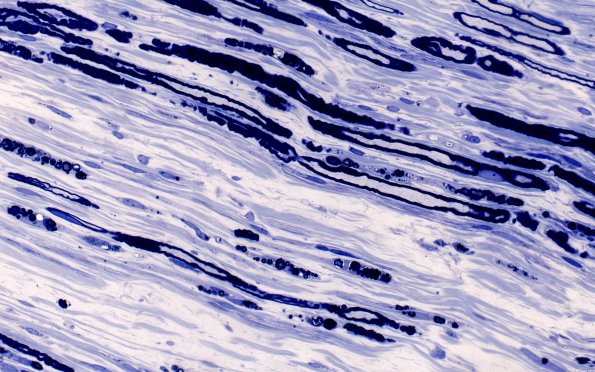

Washington University Experience | PERIPHERAL NEUROPATHY | 17 TOXIC NEUROPATHIES | Disulfiram | 1A8 Disulfiram (Case 1) Plastic 40X 1

1A8,9 These higher magnification images show numerous debris containing Schwann cells (“myelin ovoids” described in teased fiber preparations). (plastic section)